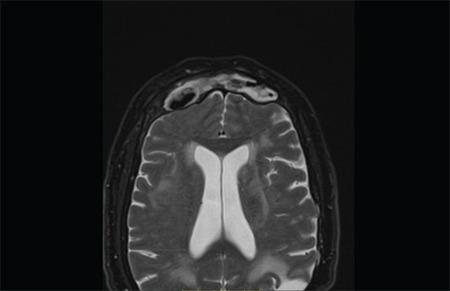

Frontal sinus keratoma or cholesteatoma is a rare disease of paranasal sinuses and presents as a slow-growing mass that becomes symptomatic as it grows to the surrounding structures. Intracranial complications are not a common presentation and are potentially life-threatening. Frequently the final diagnosis is only made intraoperatively because several other frontal sinus tumors behave likewise. Definitive treatment requires complete removal of the keratoma, and a combined endoscopic and external frontal sinus approach is a good treatment option. In this report, we presented a 68-year-old female with frontal sinus cholesteatoma with diagnostic and therapeutic features of this pathology with the review of the literature.